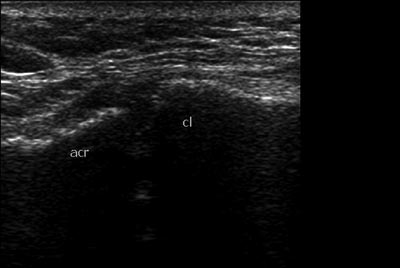

Есть ли показания для оперативного вмешательства у женщины с застарелым разрывом АКС? Женщина обратилась с жалобами на боль в области плечевого сустава на протяжении 4,5 месяцев после травмы. Боль беспокоит при подъеме руки от 45 град до 90. Также беспокоит онемение 3- 4 пальца кисти, периодически возникающий отек кисти. В сентябре после травмы диагностирован разрыв АКС слева Tossy 1, была наложена повязка Дезо. Затем периодически получала разные виды физиотерапии, мази без эффекта.Был проведен повторный Rg. На УЗИ я выявила расширение АКС до 15 мм, (на здоровой стороне суставная щель до 5 мм), содержимое неоднородное, имеется неровность дистального конца ключицы. Признаки разрыва акромиально-ключичной связки. Целостность сухожилий ротаторной манжетки сохранена. Выпота в сумках нет.Описание Рентгенолога: 1ый снимок октябрьский , второй справа -середина февраля (недавно). 1 ый снимок сделан с грузом - второй - без груза. На рентгенограмме левой плечевой кости с плечевым суставом с центрацией на левый АКС от февраля года в сравнении с рентгенограммой от октября отмечается разрыв КАС первой степени по Tossy, в динамике расстояние левого КАС с 0,7 мм и ступенеобразной деформацией увеличилась до 1,1 см (я не опечаталась - такова размерность в заключении) с признаками лизирования эпифиза левой ключицы, реакция мягкотканного компонента отсутствует.Подскажите, пожалуйста, какая же здесь степень разрыва по Tossy? Необходимо ли оперативное вмешательство, по поводу данного разрыва? Считаете ли Вы, что есть разрыв связки? Какова дальнейшая тактика ведения пациентки.